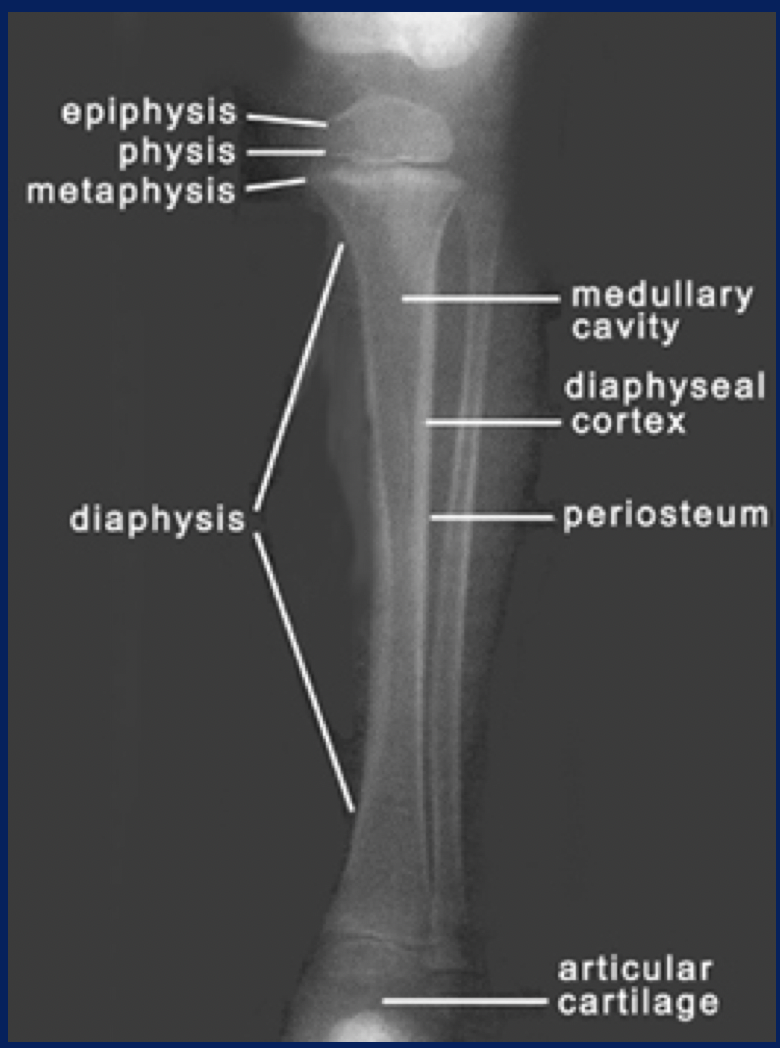

Bones increase in length by […] growth of epiphyseal plate (area of cartilage)

Interstitial

Bones increase in width by […] growth (osteoblasts lay down matrix in layers parallel to the outer surface)

Appositional